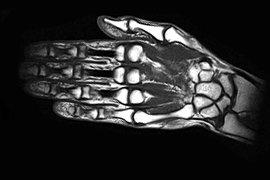

МРТ кисти руки и лучезапястного сустава

Магнитно-резонансная томография руки позволяет детально визуализировать все патологические отклонения суставов. А в некоторых случаях вы даже можете сэкономить, выполнив вместо дорогостоящей артроскопии (это диагностика и лечение повреждений внутренней части сустава) МРТ кисти и запястья. Если у пациента нет предписаний к обязательному хирургическому лечению суставов, то он вполне может обойтись обследованием на томографе. Детальное исследование позволяет с точностью диагностировать целый ряд заболеваний. Назовём лишь несколько из них: абсцесс (нарыв, гнойное образование), бурсит запястья (воспаление жидкости в между суставами, повреждение связок и сухожилий, болезнь Кинбека (нарушение кровоснабжения), переломы, повреждение мышц и т.д.

Ни один из методов обследования лучезапястного сустава не является настолько же эффективным, как МРТ. Этот способ применяется в первую очередь для диагностики травм руки, однако также может проводиться на предмет опухолей и хронических заболеваний. Благодаря самому принципу работы МРТ этот метод совершенно безопасен и не создает риска для здоровья пациента, также он неинвазивен и дает четкую визуализацию исследуемой структуры организма.

Особенности строения запястья полностью объясняют преимущества применения магнитно-резонансной томографии. Кисти рук содержат огромное количество очень маленьких костей, которые крайне плохо захватываются на рентгеновских снимках — однако МРТ имеет возможность получить полную картину их состояния. Этот метод является единственным неинвазивным, который способен с точностью определить опухолевые новообразования в тканях. МРТ является также единственным обследованием, способным выявить туннельный синдром.

Метод МРТ неивазивен, к тому же позволяет получить изображения различных плоскостей кисти, с детальной визуализацией анатомических структур запястья, пястно-фаланговой зоны и лучезапястного сустава в целом, начиная от костного скелета до мягкотканых элементов (сухожилия, связки, мышцы, сосуды, нервы), с прицельным исследованием мельчайших образований.

Что показывает МРТ исследование кисти:

- Повреждение мышц, сумочно-связочного аппарата (нестабильность лучезапястного сустава)

- Повреждение сухожилий и хрящевой ткани

- Болезнь Кинбека

- Туберкулезное поражение кисти

- Тендиниты и теносиновиты (воспаление оболочек сухожилий)

- Абсцесс мягких тканей кисти, другие инфекционные процессы

- Бурсит запястья (воспаление суставной сумки)

- Скрытые переломы, в особенности костей запястного ряда

- Остеонекроз (аваскулярный некроз костей)

- Опухолевидные образования костного и мягкотканого скелета кисти

- Компрессия и повреждение нервов

Данные состояния, диагностированные на МРТ, в сочетании с другими объективными методами позволят докторам разработать успешные подходы к лечению в каждом конкретном случае, выработать тактику и этапность оперативного вмешательства для максимально полного восстановления анатомии и функциональной активности кисти.